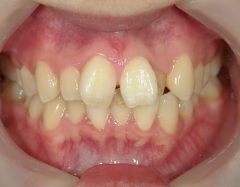

矯正歯科 治療前矯正歯科 治療前

矯正歯科 治療前

no.8_8495_治療前_左.jpgno.8_8495_治療前_正面.jpgno.8_8495_治療前_右.jpg